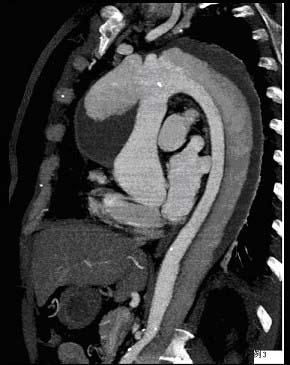

问题 请看一组主动脉的CT增强图像,正确的描述和结论是 ( )

选项 A、真腔较假腔小 B、真假腔之间线状低密度影为内膜片影 C、主动脉瘤 D、主动脉夹层 E、主动脉血栓

答案 ABD